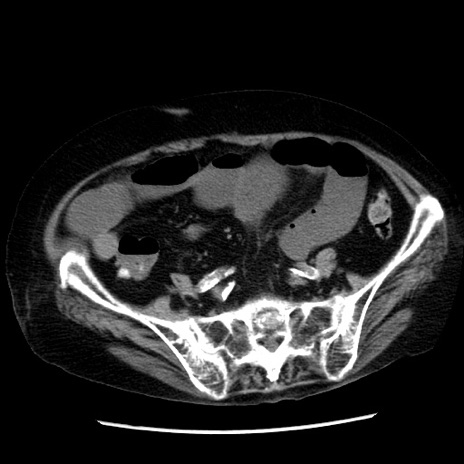

症例14(横断像)

【症例】 90歳代女性

【主訴】 腹痛・嘔吐

【現病歴】今朝から左側腹部痛を認めた。 経過観察していたが、嘔吐を認めたため来院。

【既往歴】 子宮癌術後

【身体所見】 意識清明、BP 127/54mmHg、P 98bpm Sp02 95%(RA)、BT 35.8°C、腹部平坦・軟腸ぜん動音聴取良好、右下腹部圧痛(+) 反跳痛なし

【データ】WBC 9800、CRP 0.46